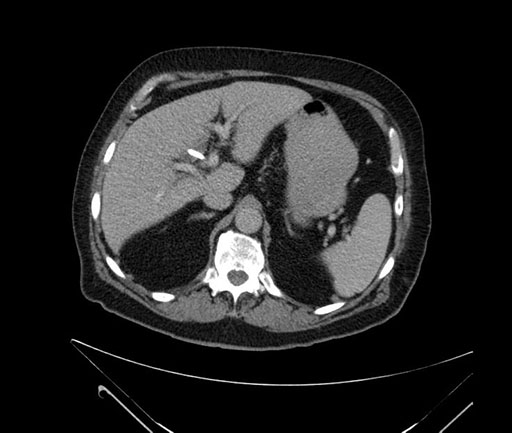

Whipple (pancreaticoduodenectomy) [case 7]

Imaging Analysis

Look through the patient's CT scan to identify any areas of concern for the necessary procedure.

Based on your CT findings, which issue(s) would give reason for "planned slowing down moment(s)" in this case?

Considering a standard Whipple procedure, what step(s) of the operation would you do differently in this case?